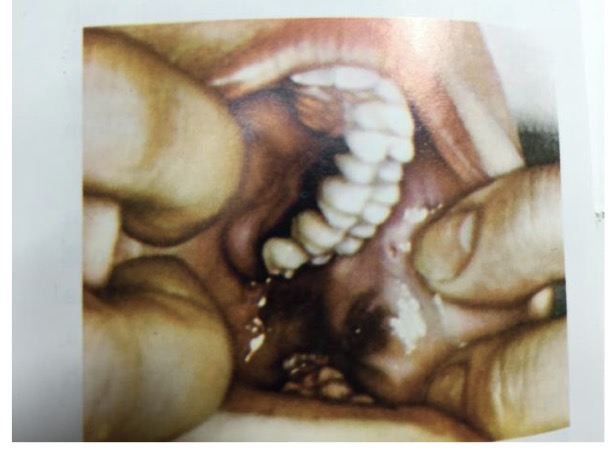

HOẠI TỬ XƯƠNG HÀM SAU XẠ TRỊ

CHẨN ĐOÁN ?